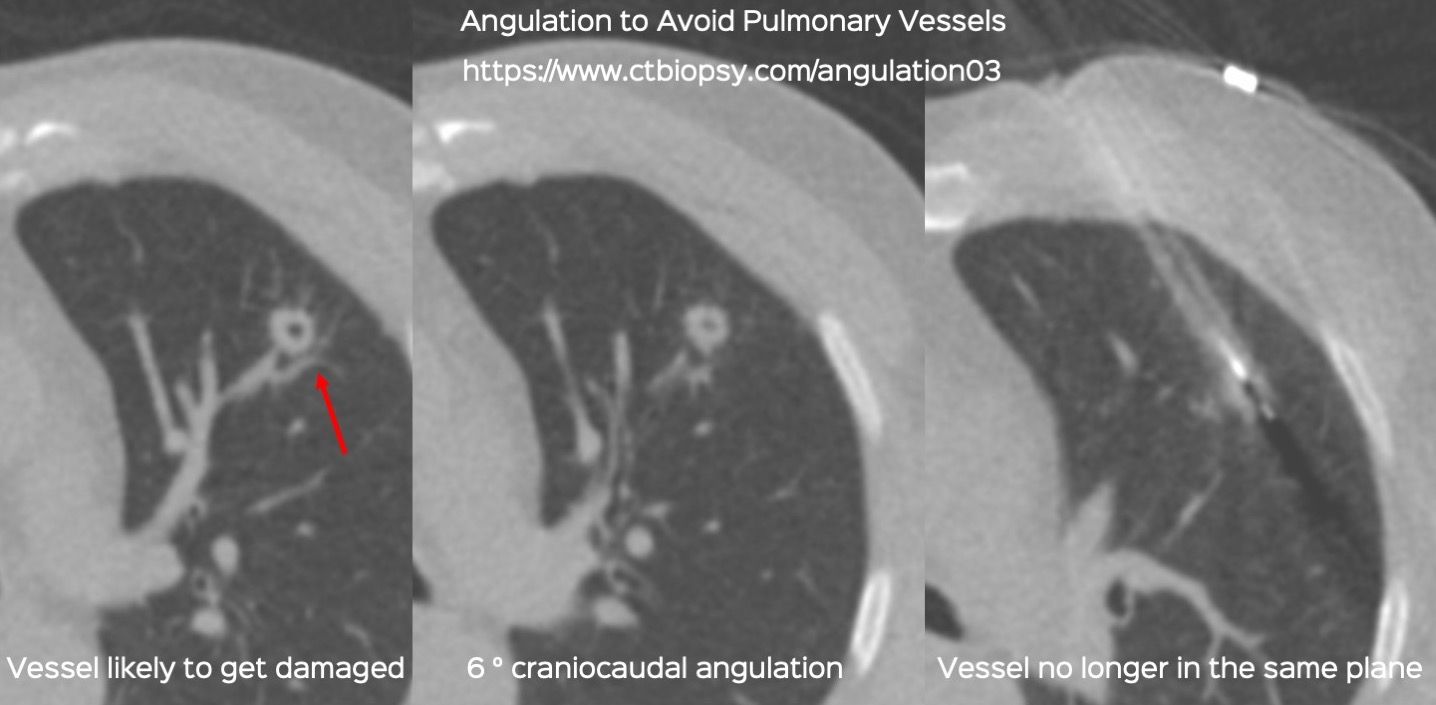

Case 83: Angulation to Avoid Pulmonary Vessels

Bhavin Jankharia - 12 March 2022